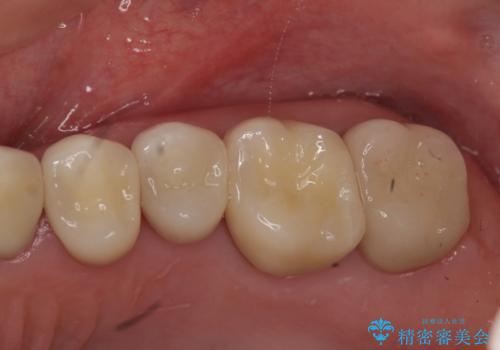

奥歯の被せ物のやり直し 精密根管治療